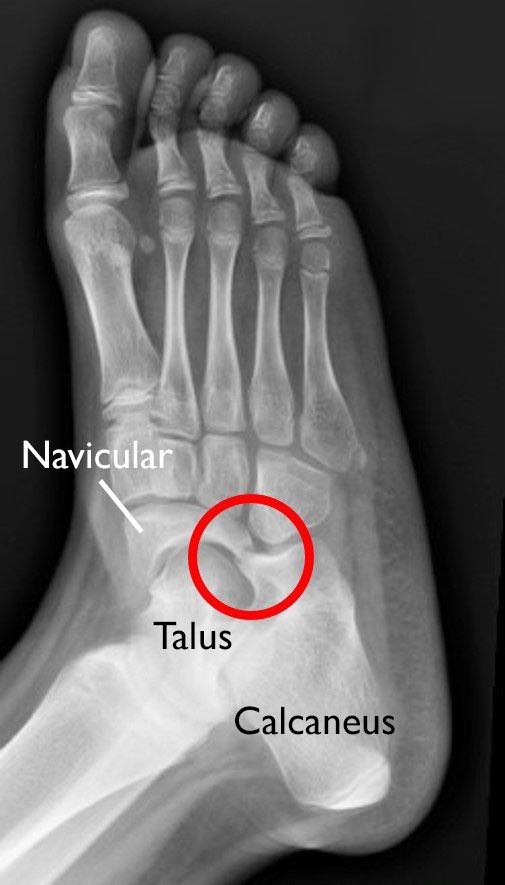

Seven bones — called tarsals — compose the hindfoot and midfoot. Coalitions can happen between any of the bones, but the calcaneus, talus, and navicular are most commonly involved in tarsal coalitions.

The calcaneus, talus, and navicular are the bones most often affected by tarsal coalition.

x-ray of a tarsal coalition

This X-ray image of a right foot shows a tarsal coalition between the navicular bone and the calcaneus bone.